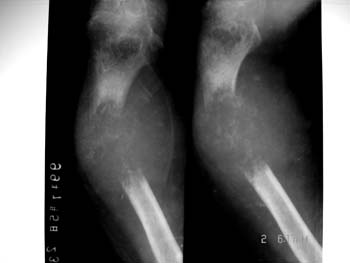

溶骨性骨破坏;

瘤骨;

放射状骨膜反应;

软组织内肿块;

病理骨折。

-------骨肉瘤

x线表现: 溶骨性骨破坏,瘤骨,病理性骨折,巨大软组织肿块。所以首先考虑溶骨性骨肉瘤。

溶骨性骨肉瘤伴病理性骨折,依据:溶骨性骨破坏,软组织肿块

该病人骨骺未愈合,很可能是溶骨型骨肉瘤伴病理性骨折。